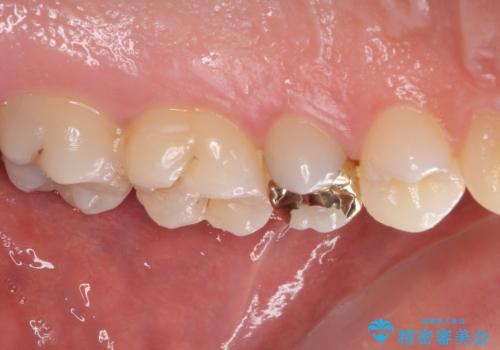

当初はセラミックインレーによる修復治療を希望されいましたが、カウンセリングの結果、審美性よりも安定性を優先され、PGAインレー(ゴールドインレー・白金加金合金インレー)による治療を行うこととしました。

仮詰め材を外すと虫歯が残っていたので、全てを取り除いた後に、ゴールドインレーの型どりを行いました。

ゴールドインレーをご自身で選択いただいたものの、どういった仕上がりとなるか不安を感じていたようですが、実際に装着された口腔内をご覧になり、思ったほど金属色が気にならないとのことでした。

咬んだ感触はご自分の歯のときと比べ全く遜色なく、患者様には大変満足していただきました。